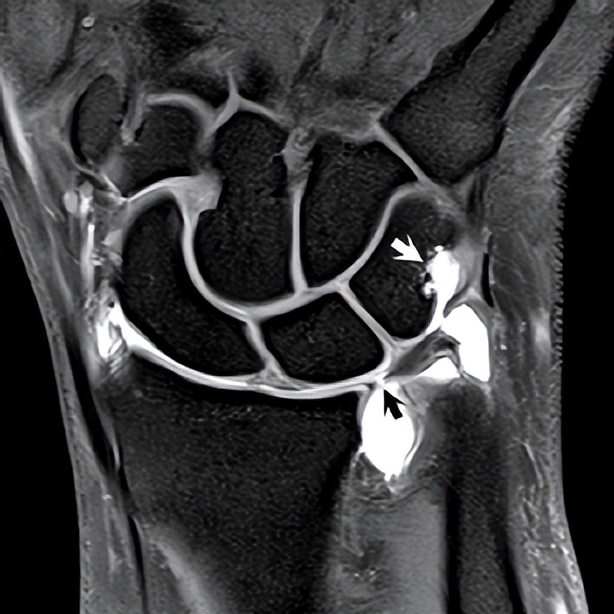

▲ 图88.1

根据帕尔默分类(Palmer分型),TFC缺损被描述为创伤性或退行性。前者通常由直接打击引起,更可能发生在TFC较厚处。由于该区域正常的不良血管分布,这种撕裂不太可能愈合,并且受伤的TFC通常被切除。这种缺陷构成了帕尔默1级病变,其中一种类型(1*级A**)在磁共振上显示如图88.1。在此FS T1WI上,低信号TFC显示1 mm的完全间断区域(黑色箭头),充满增强的钆剂。这种典型的中央全层破坏出现在TFC径向插入点内侧几毫米处。对于怀疑TFC损伤的磁共振关节造影术,最常见的是先进行单次桡腕关节注射,然后进行三平面成像用GRE采集以促进薄层成像。如图88.1所示,这种注射方式可以显示造影剂从远端桡腕关节间隙穿过破裂的TFC进入近端桡尺骨间隙。桡腕关节间隙边缘的部分撕裂显示造影剂的内渗。因为这项技术不能评估部分下表面(近端)TFC撕裂,所以也经常扫描FS T2WI。图88.1中三角骨异常信号与患者该结构的远端骨折史一致(白色箭头)。1B帕尔默病损以尺骨TFC撕脱为标志,伴有或不伴有茎突骨折。尺月韧带或尺三角韧带止点处的TFC撕裂构成1C级损伤,而将TFC从其桡侧附着处撕裂的损伤(有或无骨性撕脱)分类为1D。